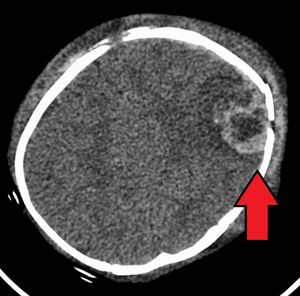

CTheatInfantAbusiveheadtrauma.png

An intraparenchymal bleed with overlying skull fracture from shaken baby syndrome